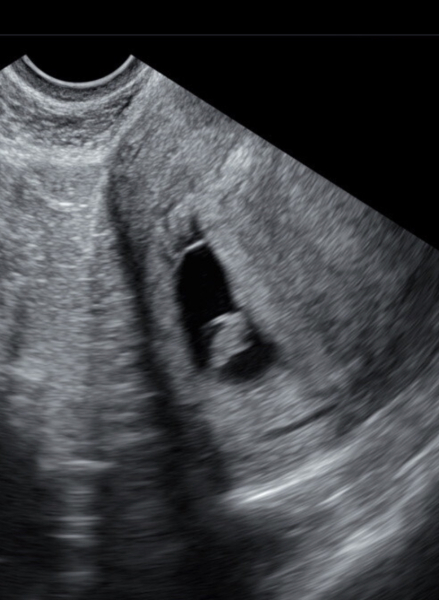

nervousn3lly · 16/02/2024 22:16

Thank you @Sunandsea13 and

Of course ❤️

@nervousn3lly what a lovely scan! I had my booking appointment yesterday- and we have the exact same due date! 😄

@nervousn3lly lovely scan photo!

@nervousn3lly beautiful scan, thanks so much for sharing 🥰

@nervousn3lly lovely scan and reassurance everything is going as it should xx